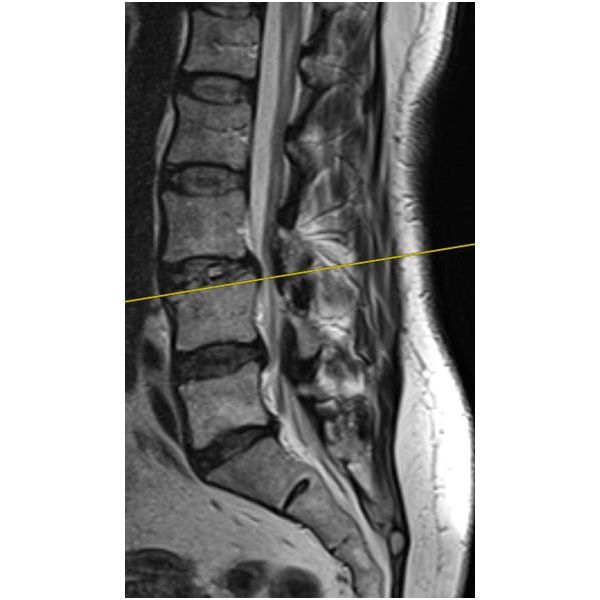

На контрольных снимках определялся цельный костный мост между позвонками L3–L4, т. е. цель операции была достигнута. Женщине разрешили больше не носить поясничный корсет, а также назначили ЛФК, физиолечение и массаж.

Учитывая неэффективность консервативного лечения в течение 3 месяцев, отрицательную динамику в неврологическом статусе, а также наличие патоморфологического субстрата на уровне L3–L4, пациентке провели малоинвазивное хирургическое вмешательство XLIF (прямой боковой спондилодез) с непрямой декомпрессией корешков спинномозговых нервов на уровне L3–L4: ей удалили старый диск и на его место установили большой широкий имплант, который позволил расширить межпозвонковое отверстие и устранить сдавление корешка.